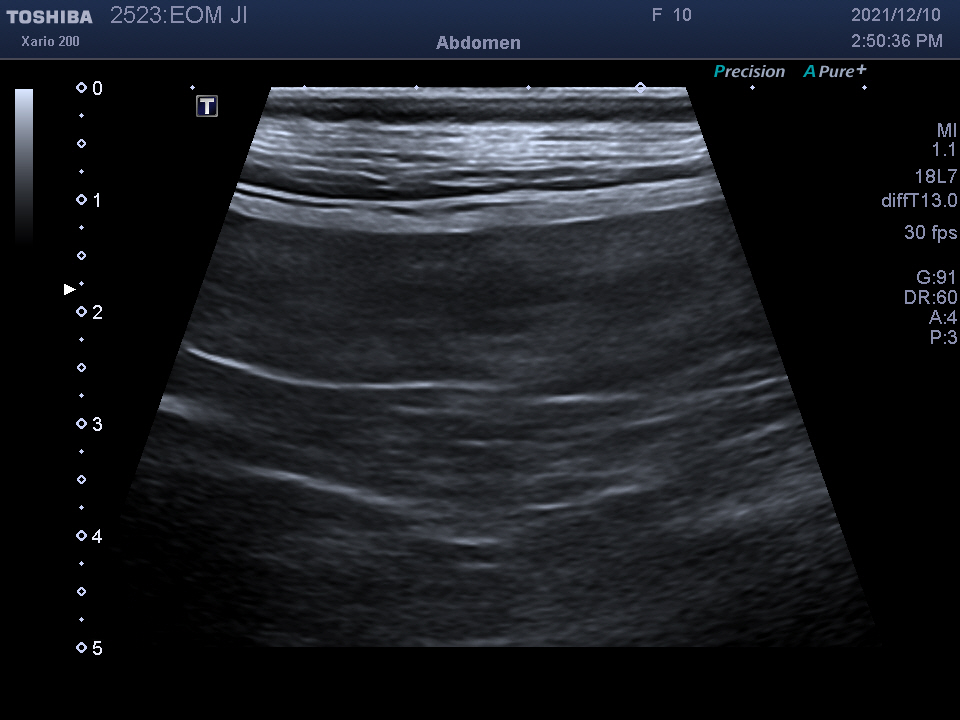

복강 내 장기를 자세히 알 수 있는

복부 초음파 검사를 진행하였습니다.

검사 결과를 종합하여 자궁 축농증이라는 진단을 받았습니다.